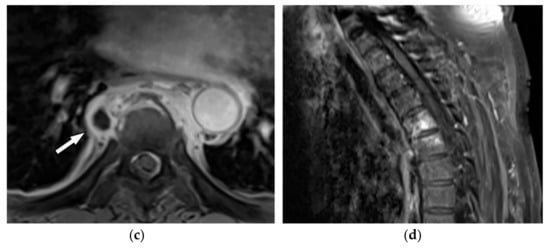

On CT, GCTs manifest as osteolytic lesions, bone expansion with cortical thinning, heterogeneous soft-tissue attenuation, and area of hemorrhage or necrosis with no internal calcification (Figure 9a,b) [30]. MRI typically reveals low to intermediate intensity on both T1-weighted and T2-weighted sequences, representing an abundant amount of hemosiderin and collagen deposition. Fluid-level occurrence is less frequent than in ABC (Figure 9c,d) [8,31]. 18F-FDG PET/CT may cause misdiagnosis of the GCT as a high-grade osseous sarcoma [30].

Figure 9.

A 52-year-old man with bilateral leg weakness and paresthesia. The axial non-contrast CT in bone window demonstrates expansile osteolytic bone lesion with destruction and collapse of the vertebral body with pressure effect over the spinal cord and paravertebral soft tissue; the edge of vertebral body cortex disappeared (arrow) (a,b). Sagittal T2W shows heterogeneous iso signal mass with the collapse of the T2 vertebral body with compression of the dura and spinal cord (arrow); anterior soft tissue mass is also shown. The Intervertebral disc was intact. The visible internal hypointense lines are caused by thickened trabecular or hemosiderin deposition (c). T1W after injection of gadolinium shows heterogeneous marked enhancement of the tumor (arrow) (d).